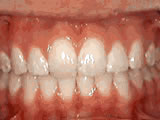

Deep overbite - Lower front teeth bite into palate

deep overbite beforeBefore

deep overbite afterAfter

This adult patient, age 25, required braces and jaw surgery to correct his severe overbite, with treatment taking two years. His problem could have been corrected without surgery if he had been treated before he was a teenager.